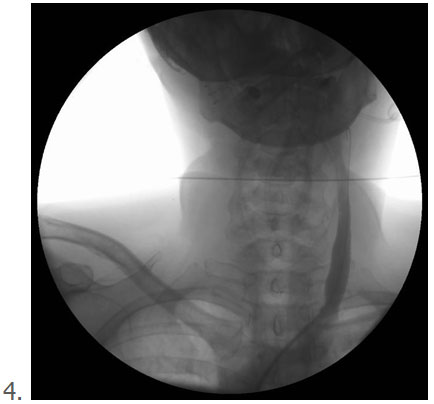

3 4

3. Ballon volledig ontplooit, dat was hier bij 14 atmosfeer

4. Controle opname na het gebruik van de ballon, goede afvoer van contrast naar het hart, ader staat breed open.

In de praktijk zie je bij het opblazen van een goed gekozen ballon, dat de ballon voor en achter het letsel eerst gaat opblazen. Goed gekozen bedoel ik de juiste diameter van ballon ten opzichte van de ader. Er blijft midden in de ballon op de plaats van de vernauwing een deuk in de ballon bestaan. Dan voert men de druk in ballon op tot deze deuk verdwenen is (meestal 12-14 atmosfeer en soms hoger). Daarna kijk je op de drukmeter waarmee je de ballon opgeblazen hebt, dan zie je meestal nog wat drukverval ontstaan omdat er toch nog een paar vezeltjes meegeven. Dan geef je opnieuw wat druk bij tot aan de druk waarop de ballon volledig is gaan open staan. En zo volg je dit voor 1-2 minuten totdat er een stabiele situatie is zonder drukverval.